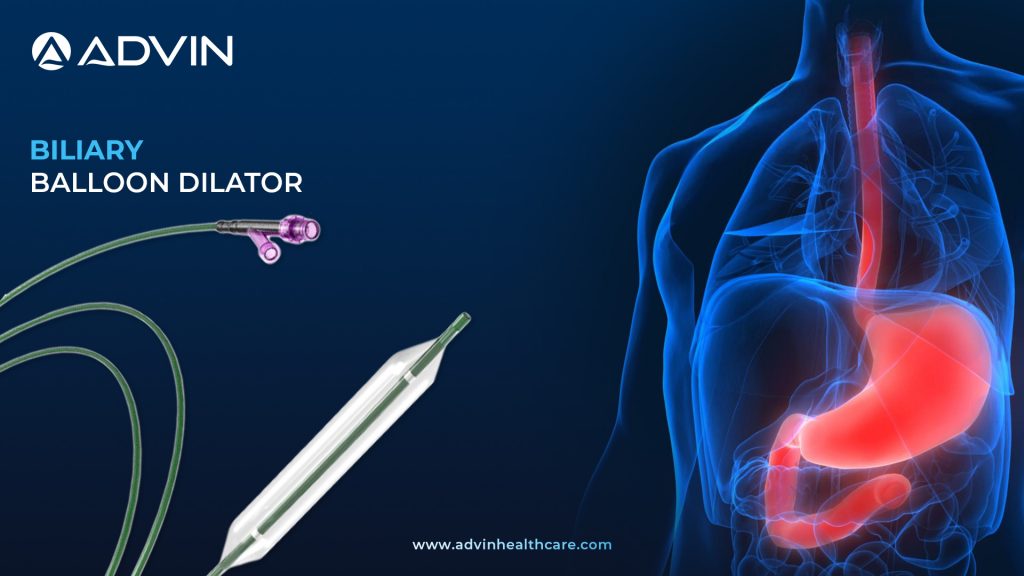

Biliary Balloon Dilator by Advin – Engineered for Accuracy

Understanding the Tool: Purpose of the Dilator in ERCP A Biliary Balloon Dilator is a medical device used to widen narrowed areas in the bile ducts during endoscopic procedures. It is introduced through an endoscope during ERCP (Endoscopic Retrograde Cholangiopancreatography). This tool helps improve bile flow by gently expanding strictures...